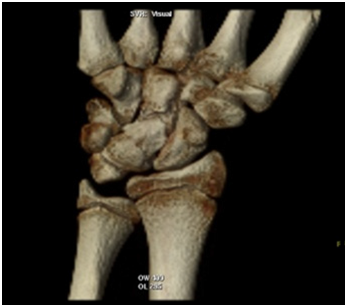

The X-rays showed the presence of a large bone tumour arisen from the lunate bone, not showing the actual involvement of the tumour in the carpal joints (Figure 2A); the subsequent CT scan confirmed the more accurate extension of the mass showing how the osteochondroma expanded dorsally and proximally, reducing and invading the ulno-carpal space (Figure 2B &2C), and also in the lateral view was easy to see how the deformed lunate had an expansion of the volar rim up to the neck of the capitate, reducing the midcarpal motion as well (Figure 2D).

Figure 2B & C 3D CT scan of the Lunate osteochondroma

Figure 2D Lateral view showing the extension of the volar rim of the Lunate  up to the neck of the Capitate.